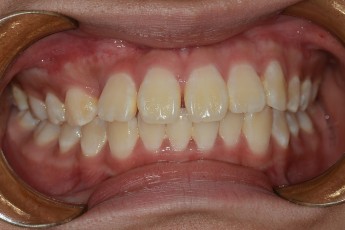

BEFORE & AFTER